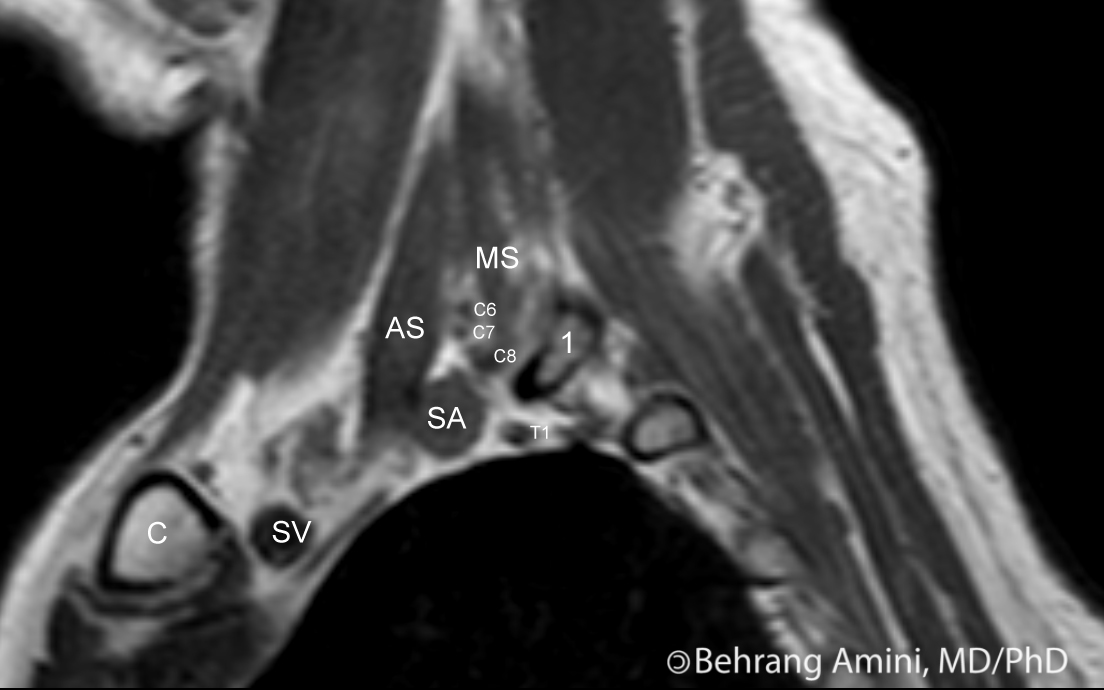

MRI neck anatomy free MRI axial neck cross sectional anatomy Mri Scalene Triangle Mri The plexus nerve roots pass through the scalene triangle, which is bordered by the anterior and middle scalene in the neck along with the first rib at the base (figure 1). The interscalene triangle is a paired structure situated at the root of the neck, with its apex pointed superiorly towards the base of the skull. The interscalene triangle, the. Scalene Triangle Mri.

2 Normal scalene triangle, sagittal plane The anterior ( AS ) and Scalene Triangle Mri The interscalene triangle, the costoclavicular space, and the retropectoralis minor space [1]. Symptoms and signs of thoracic outlet syndrome result from the. An accessory or third scalene muscle was identified in the scalene triangle in 8 cases by surgery and 4 cases by mri, yielding 50%. The horizontal base of the triangle is formed by. The plexus nerve roots pass. Scalene Triangle Mri.